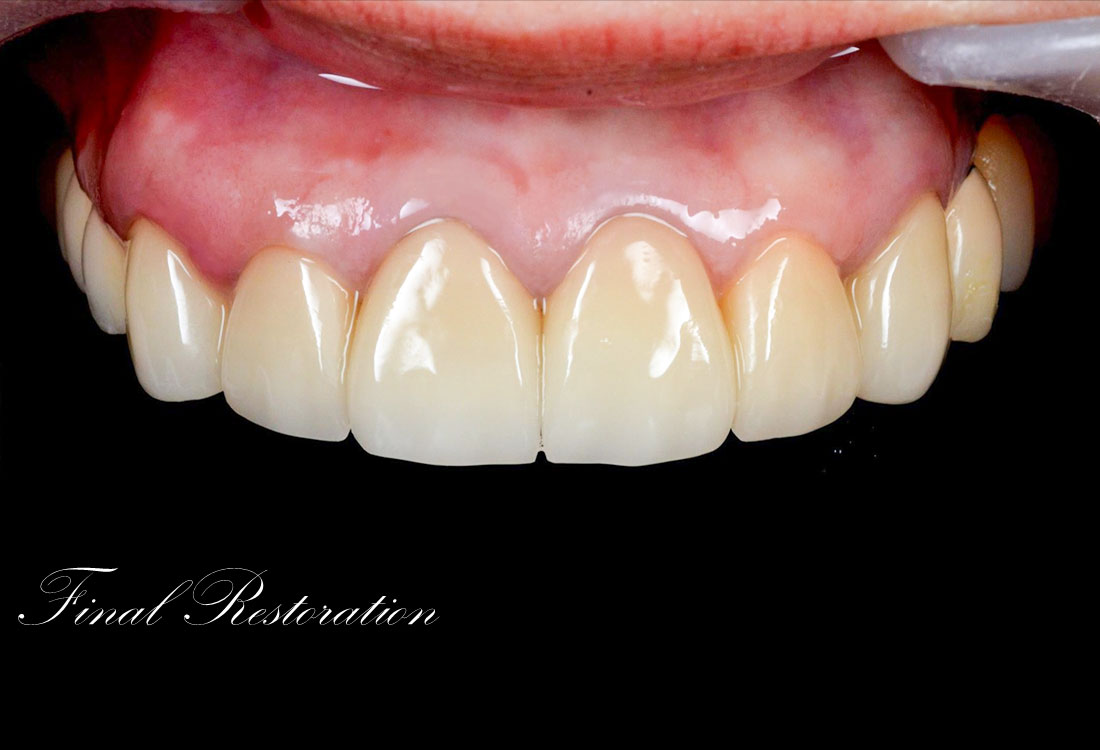

治療後

今回は前歯をグラデーションカラーのジルコニア、奥歯をセレックで治療しました。

見た目の美しさのポイントになるスマイルラインも整っています。